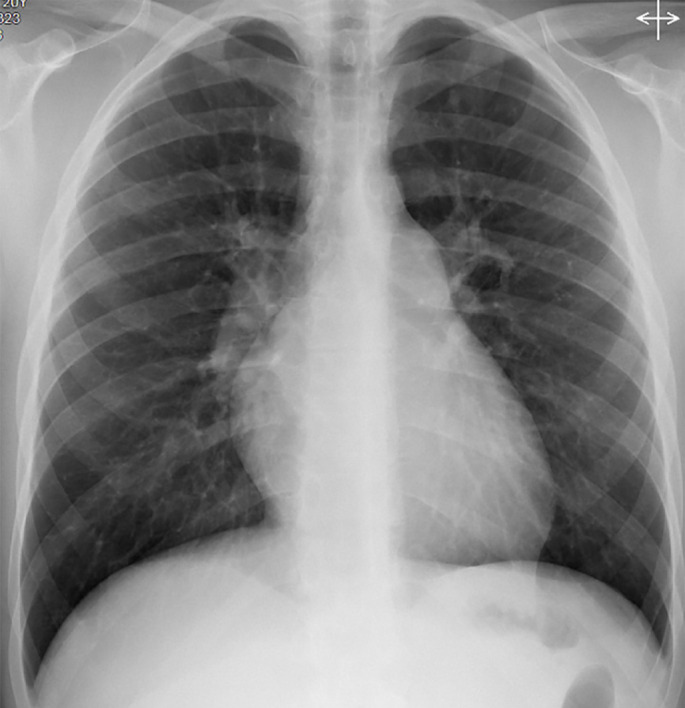

An unprecedented pathology in a 20-year-old with progressive dyspnoea and parenchymal infiltrates.

Sarcoidosis-associated pulmonary hypertension can manifest with a broad range of phenotypes. There may be a role for genetic testing in specific cases of severe disease when the relevance of comorbid sarcoidosis is unclear. https://bit.ly/42kscnz.